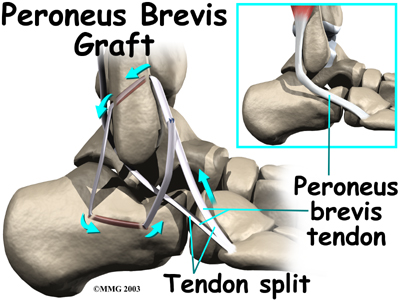

Tendon Graft Procedure

Another type of reconstruction is done using a tendon graft. If your surgeon feels that the stretched and scarred ligaments are not strong enough to simply repair in a ligament tightening procedure, then the ligaments must be reinforced with a tendon graft.

In this procedure, the surgeon removes a portion of one of the nearby tendons to use as a tendon graft. The tendon most commonly used attaches the peroneus brevis muscle to the outside edge of the small toe. A section of this tendon is put in place of the torn lateral ligaments.

After making the skin incision, the surgeon drills a hole in the fibula near the attachment of the original ligament. A second drill hole is made in the area where the ligament attaches on the talus (the anklebone).

The tendon graft is then removed (or harvested) and woven between these holes to recreate the ligament complex.

After surgery, you will probably be placed in a cast or brace for about six weeks to allow the tendon reconstruction to heal. Following removal of the cast, physical therapy will be required to regain full use of the ankle.